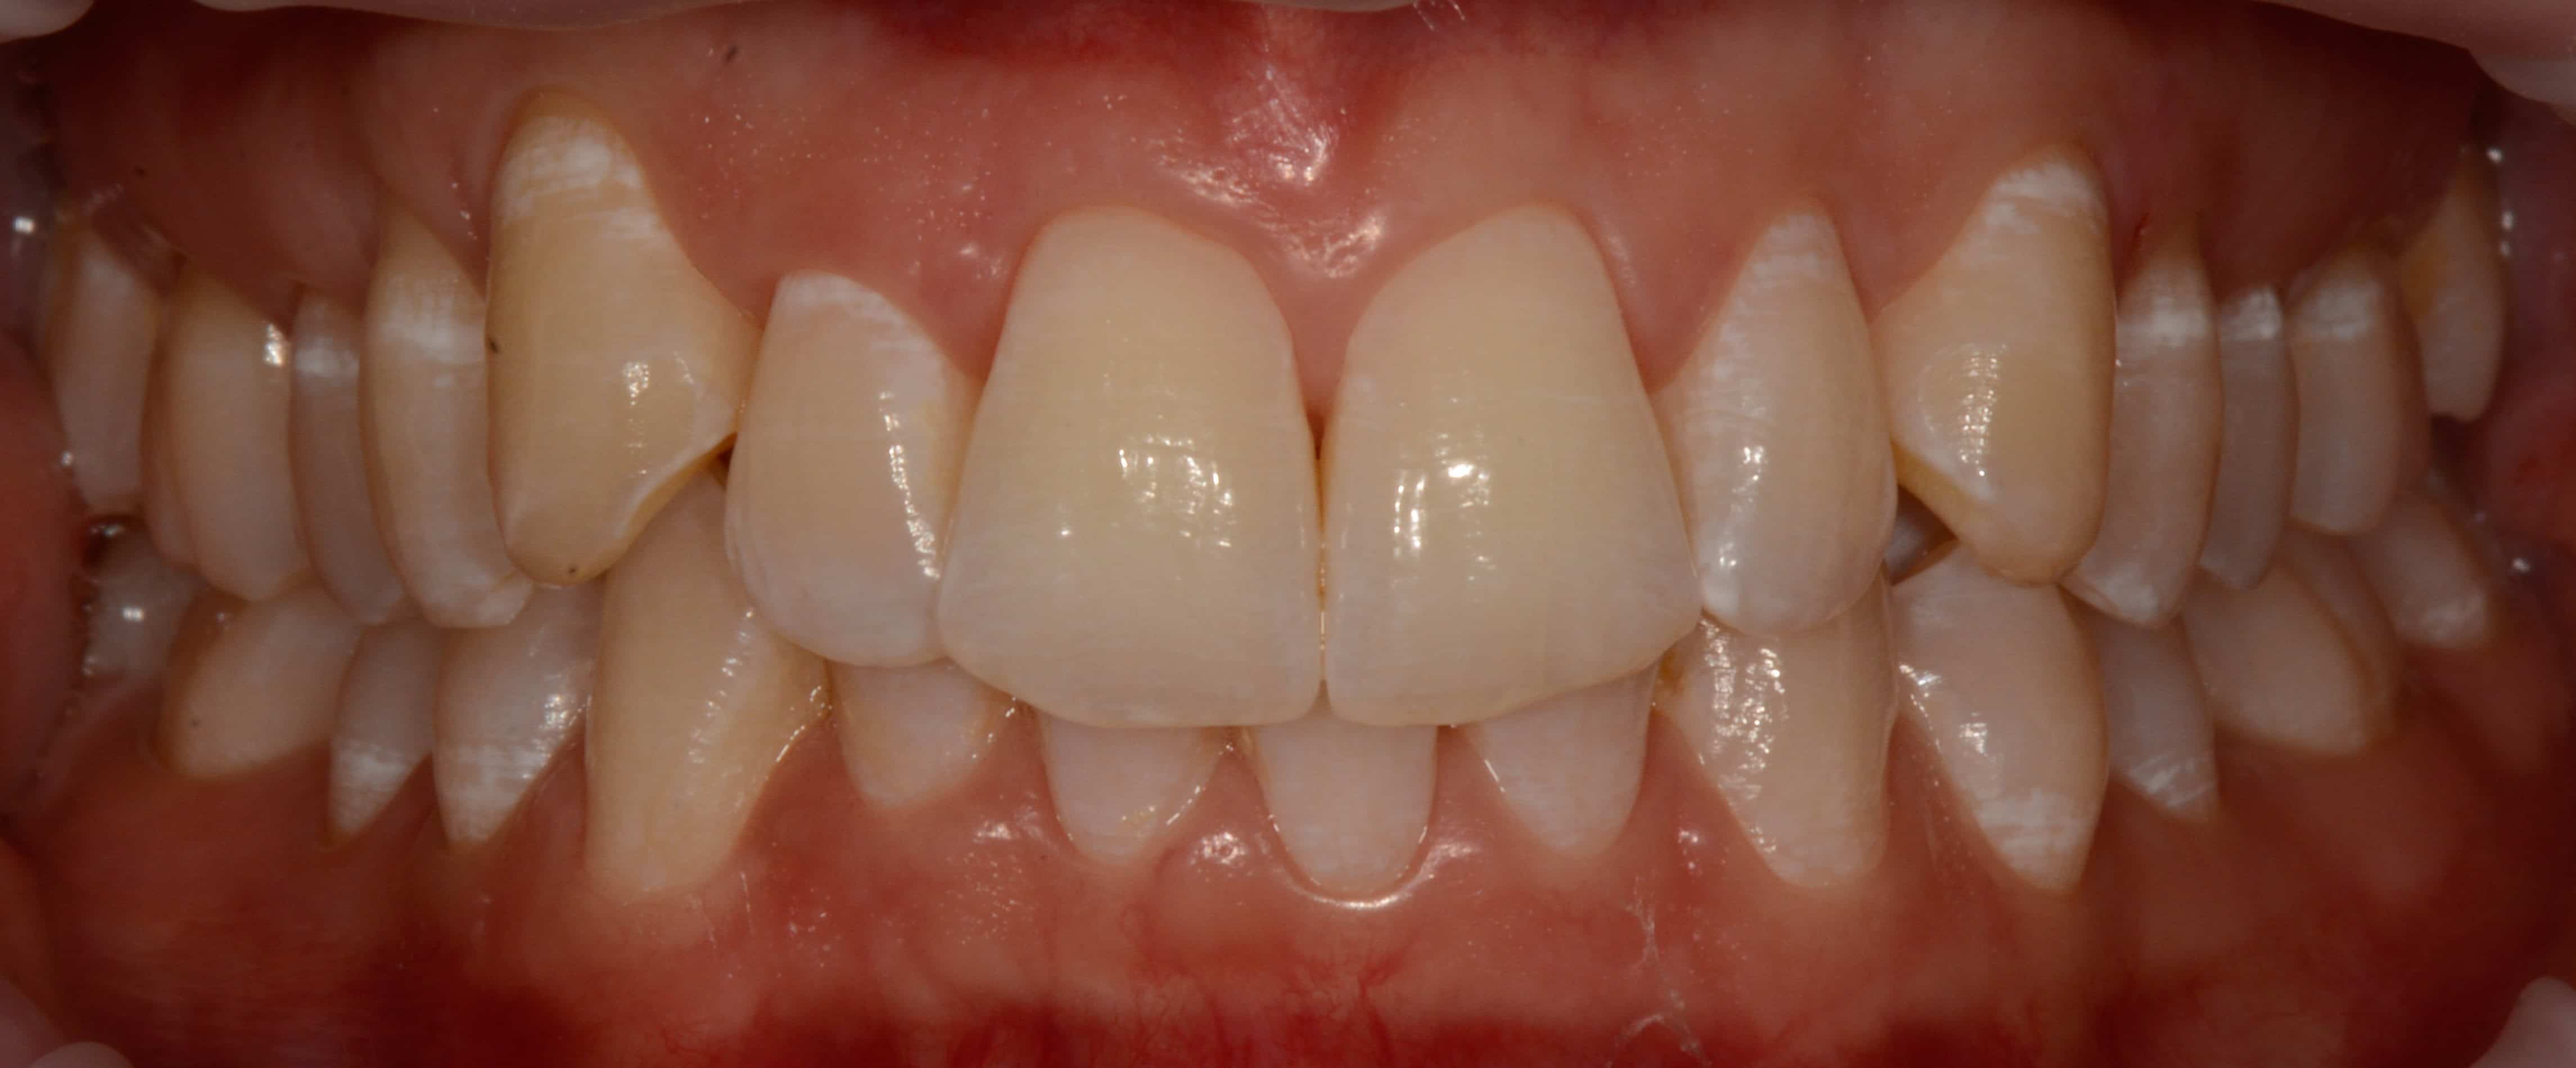

Cas #2 – retraitement avec des gouttières d’alignement